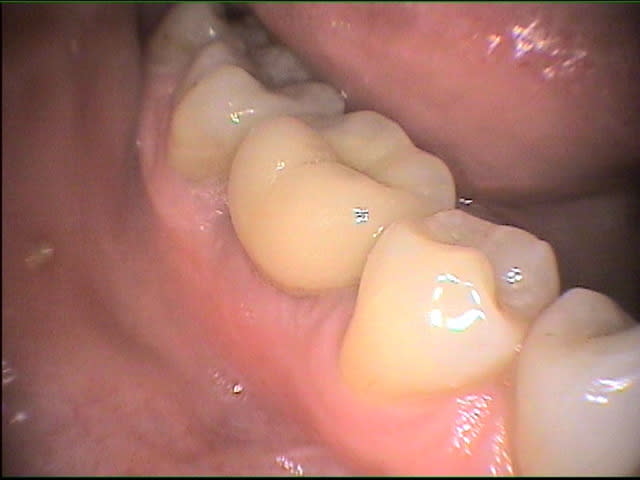

tiens, billi, qu'as-tu fait sur la 46 avec la fêlure MD?

les photos que j'ai mises sur eugenol sont extraites de mes fiches patient "DEMO" et très franchement je ne me souviens pas du cas;ma conduite en général face aux fêlures est 1-essayer de conserver 2-l'expectative ...mise sous provisoire et voir...si pas de signe clinique ou radio.. defnitif...j'aime bien les onlays métal servant de cerclage...le patient est averti;la taille de la fêlure sur la photo n'est pas très encourageante; la caméra révèle bcp de fêlures qu'on ignore